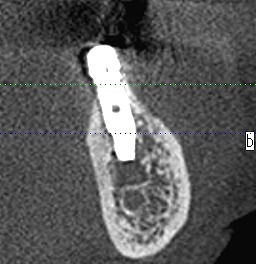

左下の6番部になります

6番部になります

インプラントの埋入位置も制限され神経までの距離も近くなります